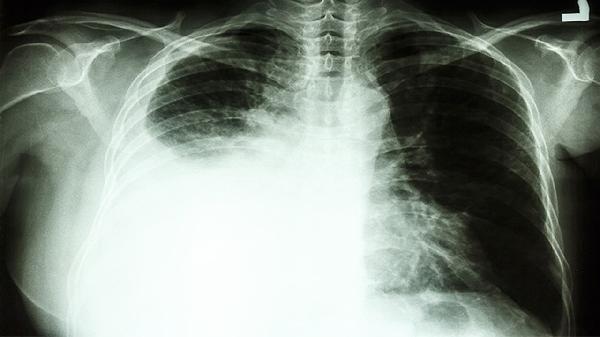

1、5毫米是警戒线

体检发现小于5毫米的微小结节,每年复查一次即可。但超过这个尺寸,特别是伴有毛刺、分叶等特征时,3-6个月就要追踪观察。

2、变化速度藏玄机

结节在短期内快速增大要高度警惕。有位患者8毫米的磨玻璃结节,半年后突然长到1.5厘米,手术证实是早期腺癌。

3、位置决定风险

靠近胸膜的结节更容易早期出现症状,而肺门附近的结节往往发现时已错过最佳干预时机。

1、检查方式有讲究

普通胸片可能漏诊小结节,低剂量CT才是金标准。复查时最好在同一家医院进行,方便对比影像变化。